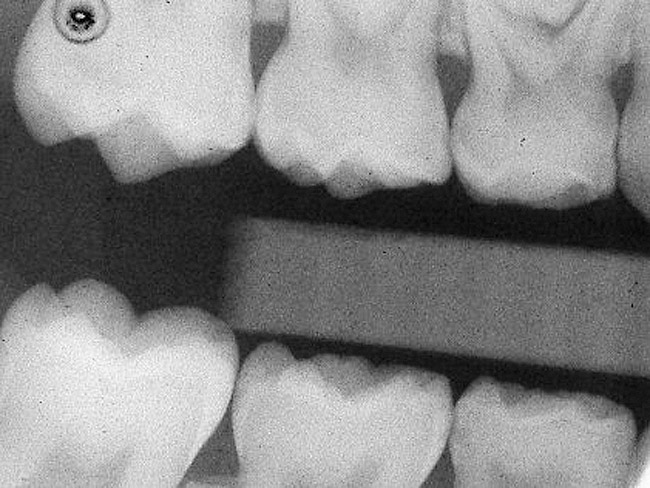

Figure 2  Preoperative radiograph showing mesial incipient lesion on tooth A.

Figure 2

Caries infiltration is indicated for all age groups, up to the first third of dentin (D-1) (Figure 2). It is especially advantageous in interproximal areas, where a relatively large ratio of healthy hard tissue must be removed to eliminate carious tissue. Infiltration replaces hard tissue lost due to demineralization (to a maximum of 800 µm) with a low-viscosity resin, creating a barrier to further diffusion of carbohydrates and organic acids within the hard tissue, not on the tooth surface. This barrier stabilizes and effectively blocks the caries without changing the anatomic shape or appearance of the tooth.85 Additionally, treated lesions lose their whitish opaque color and blend with surrounding natural enamel, which is especially esthetic in the smooth surface type of lesions often found when fixed orthodontic appliances are removed (Figure 3 and Figure 4).